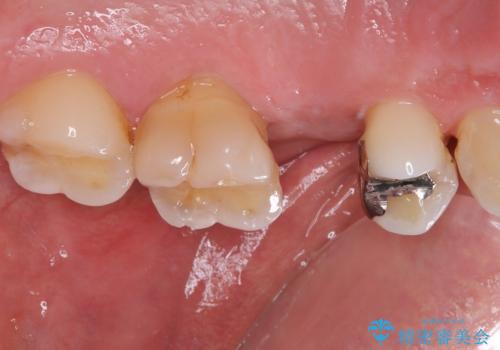

埋入から2ヶ月ほどでインプラントの十分な生着が認められ、処置した歯肉も綺麗に治癒したため、速やかに補綴治療を行いました。

補綴治療後3ヶ月での経過は良好で、引き続き経過観察を行っていきます。